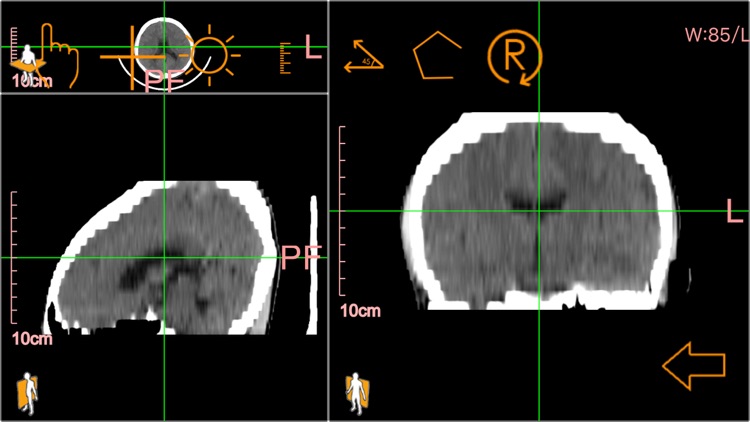

医学影像查看:可查看标准dicom格式的医疗影像。

医学影像查看:可查看标准dicom格式的医疗影像。

医学影像查看:可查看标准dicom格式的医疗影像。